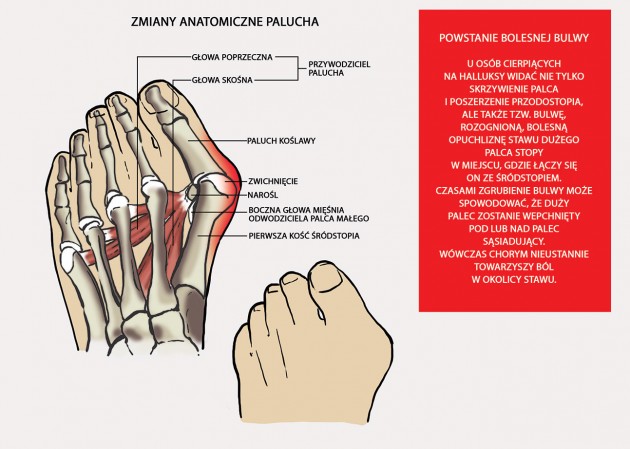

Paluch koślawy (hallux valgus)

Paluch koślawy to deformacja dużego palca, a ściślej stawu śródstopno-paliczkowego palucha (MTP). Uszkodzenie polega na szpotawym ustawieniu I kości śródstopia oraz koślawym palucha. Deformacja może rozpoczynać się w obrębie palucha lub kości śródstopia w przypadku stopy poprzecznie płaskiej.

Paluch koślawy najczęściej obserwowany jest u kobiet i może występować rodzinnie.